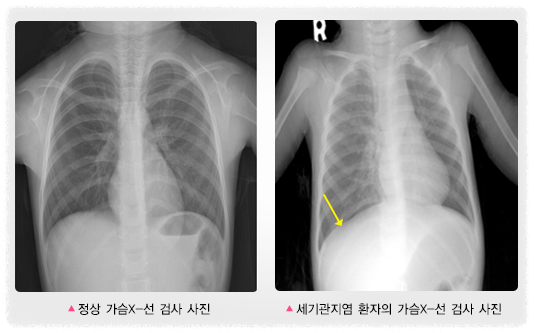

1️⃣가슴X-선 검사

- 가슴X-선 검사는 모든 환자에게 시행할 필요는 없지만 증상이 심해 입원해야 하거나, 특히 열이 있다면 폐렴이 동반되었는지 확인하기 위해 시행한다. 좁아진 세기관지를 통해 공기가 잘 빠져나오지 못하므로 폐 전반에 걸친 과팽창 소견을 보인다.

- 환자는 이물 흡입으로 인해 기관지나 세기관지가 막혀 천명이 발생할 수 있는데, 세기관지염으로 오인할 수 있으므로 병력 청취와 진찰 소견으로 이물 흡입이 의심된다면 이 때 가슴X-선 검사를 시행하여 확인한다.

위의 사진을 보면, 오른쪽 세기관지염 환자의 가슴X-선 검사를 보면 왼쪽 정상 사진에 비해 가로막(횡경막)이 밑으로 화살표 모양처럼 쳐진 변화가 보이고 폐의 과팽창을 볼 수 있다.